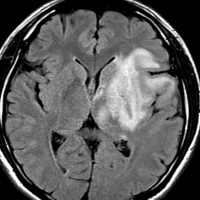

pseudoprogression スード・プログレッション

放射線治療の4ヶ月後くらいから腫瘍が大きくなりはじめ,麻痺が悪化しました。画像は放射線治療9ヶ月後のものです。腫瘍は大きくなって,周囲の脳浮腫が悪化して,閉塞性水頭症になっています。この間,大量のリンデロンを使いましたので,ステロイド治療の副作用で肥満になりました。この例のような,のう胞性拡大のようにみえるスードプログレッションは毛様細胞性星細胞腫の放射線治療後に特徴的に生じるものです。

この時点で再燃(再発)と間違って,あわてて危険な開頭手術をしてはなりません!